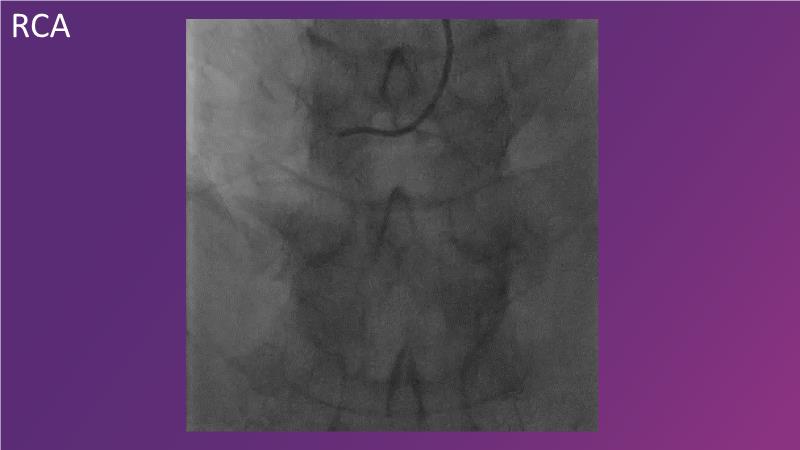

Explore the latest trends in percutaneous coronary intervention (PCI) in this session, focusing on stentless PCI and the role of sustained limus release technology. Join the discussion on how sustained limus release can expand the indications for drug-eluting balloons (DEB) and minimize the use of metal stents, gain insights into the importance of vessel preparation and learn which tools to utilize in specific scenarios.

- To learn about the importance of vessel preparation and which tool to use when

- To review clinical scenarios when a stent is not required